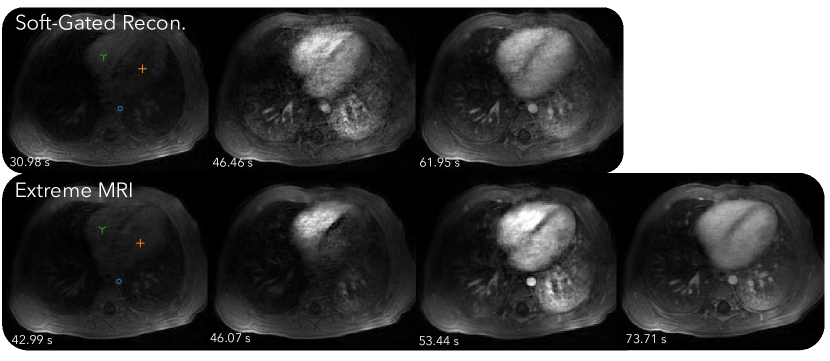

Figure 6 and Supporting Information Video S7 and S8 compare the proposed method with the soft-gated reconstruction. From Supporting Information Video S7, the proposed reconstruction shows regular respiratory motion in the beginning, but after contrast injection, breathing becomes more rapid and the patient body shifts to the right seven times. While the image quality during these bulk movements degrades, it improves as soon as the patient body returns to the original position. Similar to the first DCE dataset, distinct phases of contrast enhancement to different organs can be seen, whereas the soft-gated reconstruction merges all dynamics into one frame, including the bulk motion. From the signal intensity curves in Figure 7, the peak contrast enhancements are higher for the proposed reconstruction than for the soft-gated reconstruction. Dips in the signal intensity curves in later parts of the scan can be seen for the proposed reconstruction, which corresponds to when bulk motions occur. A motion adjusted plot was created by manually tracking the voxels over time. Variations due to bulk motions in the signal intensity plots are mostly removed after motion adjustment.

Figure 4, 6, and 8 all show that the proposed reconstruction displays much finer dynamics that are not represented in soft-gated reconstructions with low frame-rates. Distinct phases of contrast enhancements in different organs can be seen, which are more physiologically accurate. The benefits of higher temporal resolution can also be seen from signal intensity curves. In particular, signal intensity peaks of the aorta are much higher in the proposed reconstruction, but are averaged out in the soft-gated reconstruction. While bulk motion still affects the overall image quality as shown in Figure 6, the proposed reconstruction allows us to retrospectively adjust for bulk motion when computing the signal intensity curves, which can be useful for quantification purposes.